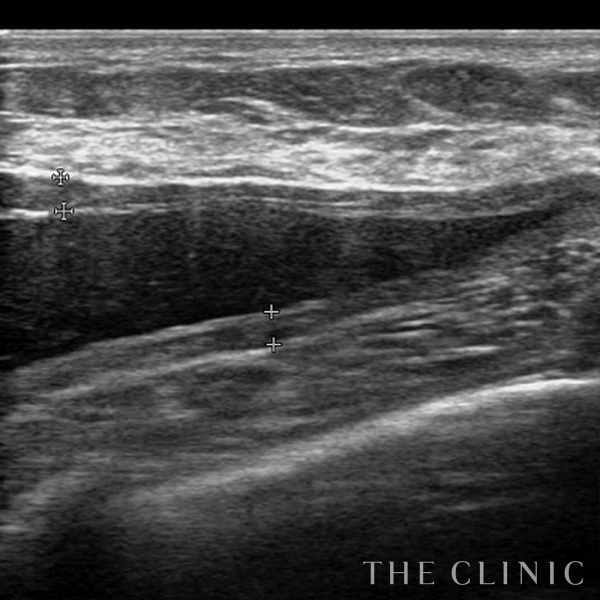

コンデンスリッチ豊胸を行うために、前もってアクアフィリングの除去を行いました。エコーで確認するとかなり厚い被膜が形成されています。

アクアフィリングは生理食塩水で溶解されるとのことで、エコー下に生理食塩水を注入しましたが、なかなか溶解できず、ヒアルロニダーゼも追加してなんとか溶解除去することができました。右側は炎症があった為か、汚く濁った状態でした。